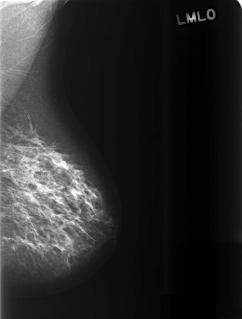

C_0471_1.LEFT_MLO

LEFT_MLO LINES 5416 PIXELS_PER_LINE 4112 BITS_PER_PIXEL 12 RESOLUTION 50 NON_OVERLAY